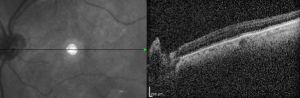

Historically, the diagnosis of foveal hypoplasia was made in nystagmus evaluation with the ophthalmoscopic examination of the fundus. Findings commonly included the absence of foveal pigmentation and the foveal reflex.[6][9] Introduction of fluorescein angiography allowed for visualization of the FAZ, and a small or absent FAZ coupled with ophthalmoscopy support the diagnosis of foveal hypoplasia.[9] Non-invasive imaging such as OCT and OCT-A (optical coherence tomography angiography) are now commonly used to evaluate the morphology and vasculature of the retina, respectively. In foveal hypoplasia, OCT evaluation reveals the absence of the foveal pit and the persistence of inner retinal layers through the area where the foveal center is expected.[2][32] OCT-A evaluation of the FAZ shows an absence at the superficial capillary plexus and a variable decrease in the deep capillary plexus.[33][34]

Grading

OCT provides high-resolution images of the retinal layers and has aided in the morphologic characterization of foveal hypoplasia. In 2011, Thomas MG et al. developed an OCT-based grading system for foveal hypoplasia based on unique foveal specialization features visible on OCT ( see table ).[35] This Leicester Grading system has been validated in several studies[18] and has recently also been shown to predict future vision in children with infantile nystagmus.[36]